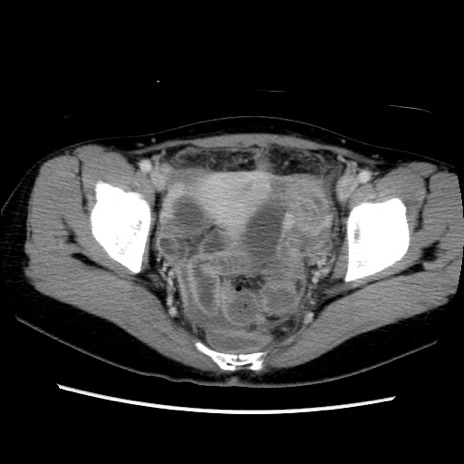

症例39(横断像)

【症例】40歳代女性

【主訴】上下腹部痛

【現病歴】2日目から下腹部痛あり。夜間は痛みで眠れなかった。昨日より上腹部痛と下痢が出現。臥位で痛みは軽快したため、休んでいた。本日になって臥位でも立位でも痛みが強くなってきたため救急要請。

【既往歴】子宮内膜症

【身体所見】部:平坦・軟、左上下腹部に圧痛あり、反跳痛あり。

【データ】WBC 21800、CRP 26.78